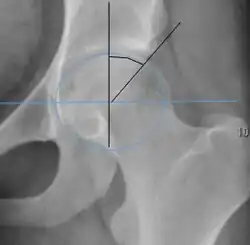

| Crossing ratio |

|

Percentage of acetabular walls crossing. Normal acetabulum is oriented in anteversion. Its value ranges from 15 to 20° in the equatorial plane of the acetabulum and decreases gradually towards the acetabular roof, where normal values range from 0 to 5°. Retroversion of the upper part of the acetabulum has been related with pincer type impingement. In radiography the presence of a "crossover sign" is produced when the posterior wall of the acetabulum crosses the anterior wall before reaching the acetabular roof. It is a sign of acetabular retroversion and it has been linked with overcoverage and pincer impingement. Nevertheless, this sign has been described in 6% of the normal population. Therefore, more important than its presence is the percentage of crossing. | <20%